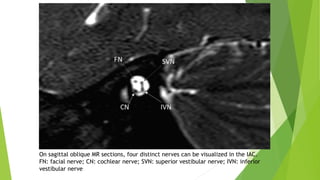

On sagittal oblique MR sections, four distinct nerves can be visualized in the IAC.

FN: facial nerve; CN: cochlear nerve; SVN: superior vestibular nerve; IVN: inferior

vestibular nerve

On sagittal obliqueMR sections, four distinct nerves can be visualized in the IAC. FN: facial nerve; CN: cochlear nerve; SVN: superior vestibular nerve; IVN: inferior vestibular nerve